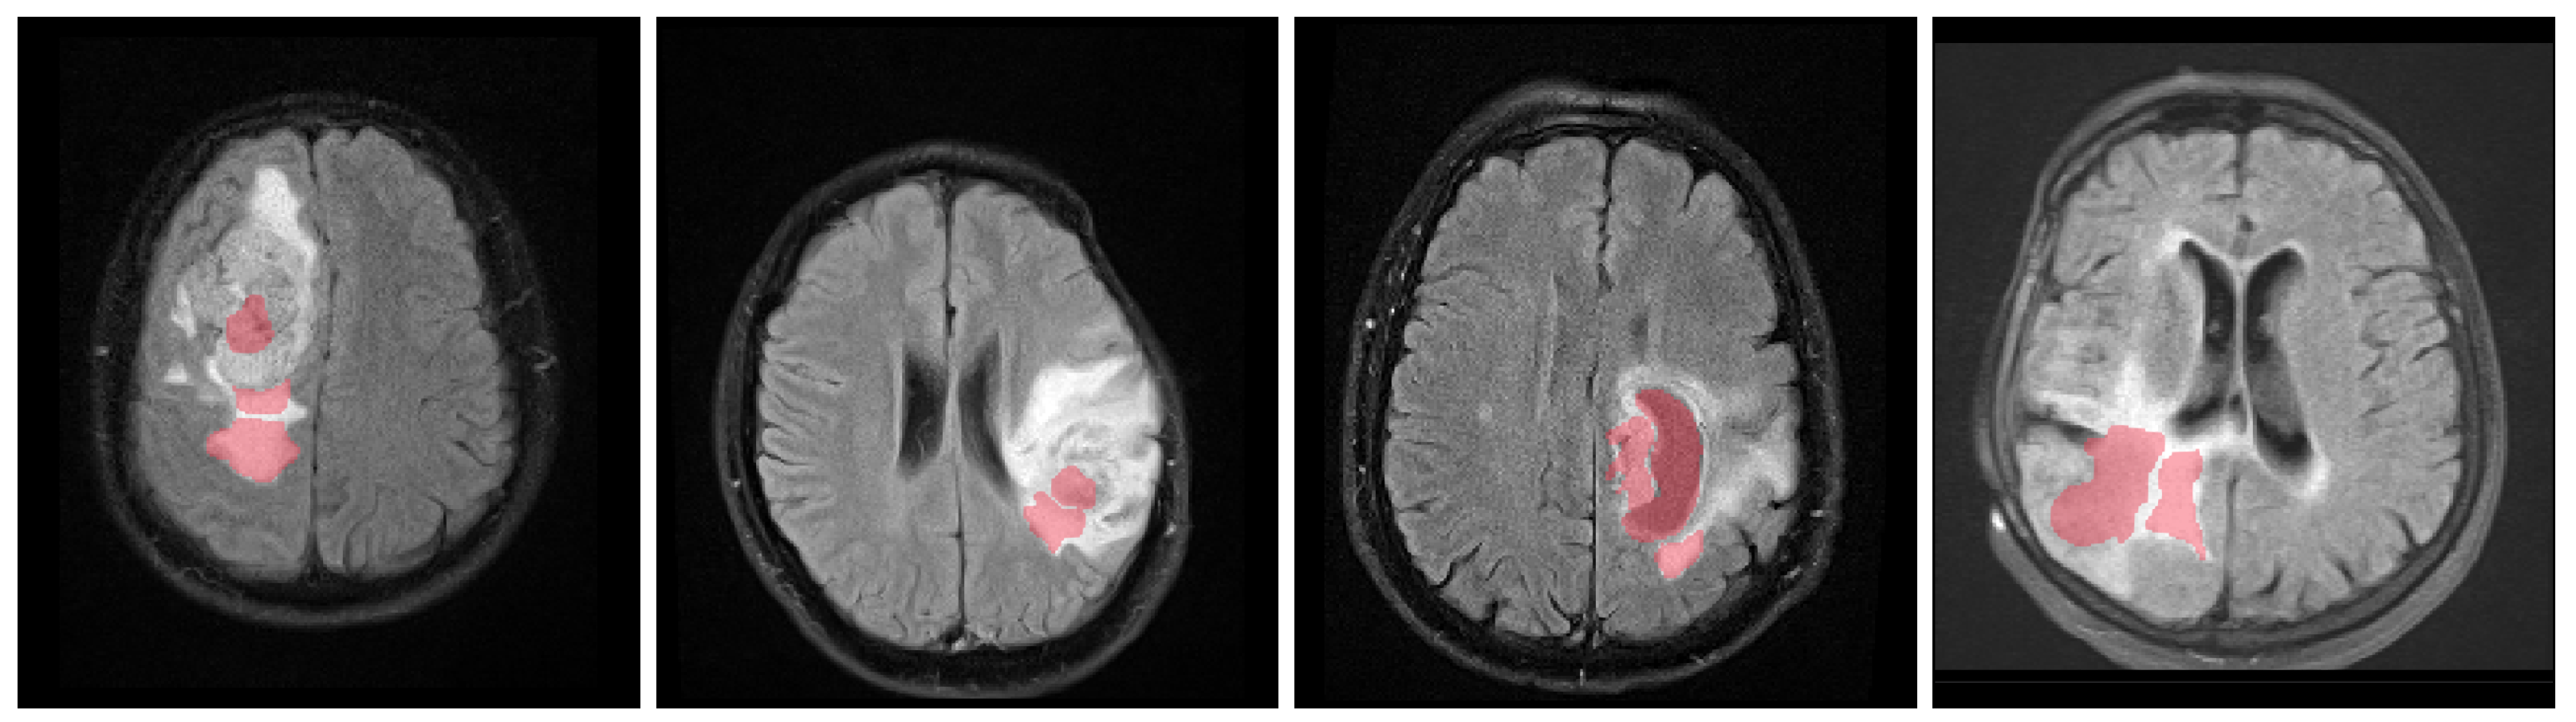

The obtained mean DICE score from leave-one-out experiments is 78.7% ± 15.7%, and the sensitivity and specificity are 78.3% ± 15.9% and 98.8% ± 1.2%, respectively. These results are inline with the expected results from other experiments and could be further improved using more sophisticated features and additional post-processing [17]. Figure 7 shows some examples of the obtained segmentation, both as two and multiclass results.

Figure 7.

Example axial and coronal (HG 006) slices from the validation set u(BraTS 2013 dataset) using the proposed PU-learning method. The colour coding is as follows: ‘yellow’: edema; ‘red’: enhancing tumour; ‘green’: non-enhancing tumour; ‘blue’: necrosis. The subject name is identical to the identifier within the original training dataset.